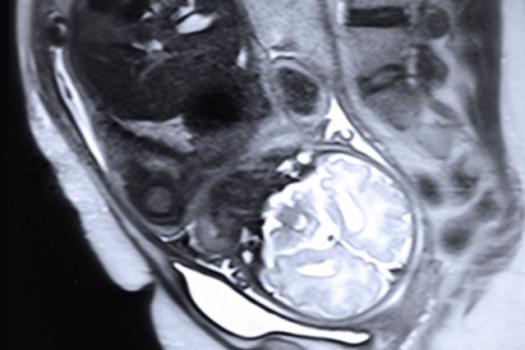

We build computational models of anatomical and functional variability from medical images and develop methods for making predictions for new subjects based on images and prior information. We collaborate extensively with practicing clinicians, clinical researchers and neuroscientists to apply these methods in surgical planning and navigation, population studies and basic neuroscience.